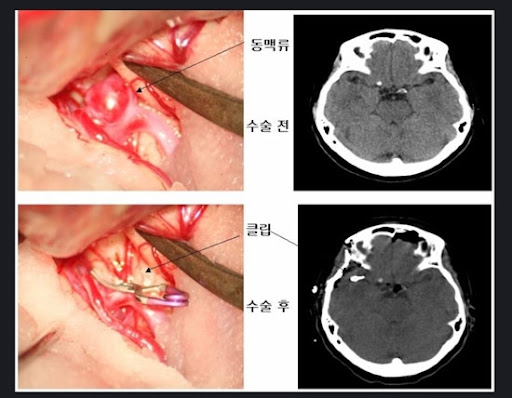

개두술 및 동맥류 결찰술

이 방법은 두개골을 열고 현미경을 이용하여 동맥류의 목 부분에 클립을 장착하여 혈류를 차단하는 수술입니다. 이 수술은 파열된 동맥류의 재출혈을 방지하는 데 효과적입니다. 수술 후에는 중환자실에서 경과를 관찰하며, 환자의 상태에 따라 일반 병실로 이동합니다. 입원 기간은 보통 7~10일 정도이며, 회복 기간 동안 통증과 불편감이 있을 수 있습니다.